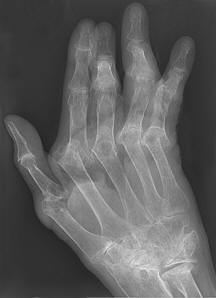

Normal hand RA - Damaged finger joints RA - Fused finger joint

Normal hand bones RA - Damaged hand bones RA - Damaged hand

https://commons.wikimedia.org/wiki/File:RheumatoideArthritisAP.jpg

Description   Typisches Röntgenbild einer

Rheumatoiden Arthritis.

https://commons.wikimedia.org/wiki/File:Rheumatoide_Arthritis_der_Hand_65W_-_CR_ap_-_001.jpg

Description      Deutsch: Rheumatoide Arthritis der Hand. Zusätzlich Fingerfrakturen.